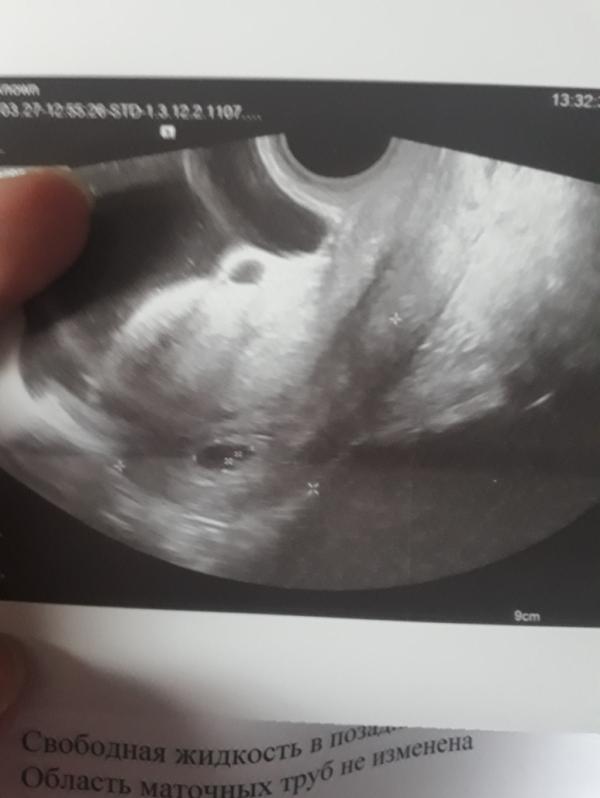

Может кто разбирается?))вроде в порядке все)))на месте бусина,там где положено ❤

Мне кажется норма у меня только сейчас показало что эмбрион есть сердцебиение есть. По узи срок 6.5. Так что думаю все хорошо у вас просто маленький срок

У меня так же на 6,1 было в воскресенье . Пойду в это воскресенье теперь делать в 7,1